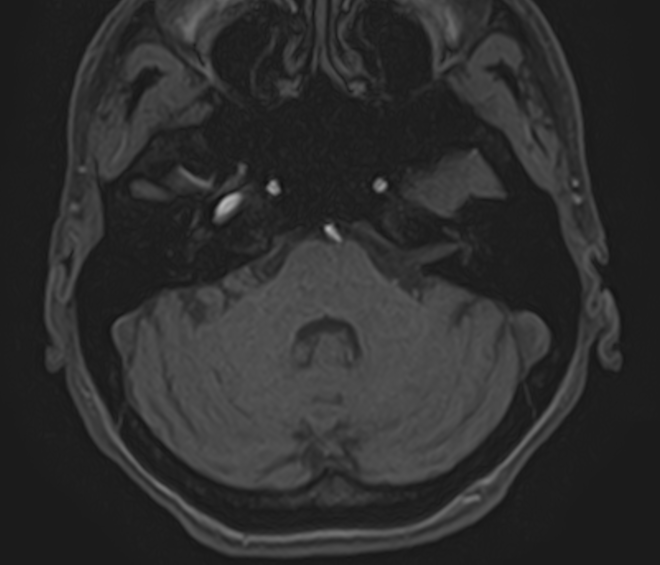

Специальной подготовки для проведения исследования не требуется. Перед процедурой необходимо снять украшения, заколки с области головы.

Абсолютными противопоказаниями к проведению МРТ внутреннего уха являются несовместимые с МР-системами кардиостимуляторы /водители сердечного ритма, импланты внутреннего уха, инсулиновые помпы, а также клипсы на сосудах головного мозга, металлические осколки в теле пациента. К относительным противопоказаниям относятся: беременность (первый триместр), клаустрофобия, зажимы и клипсы на сосудах внутренних органов.

При наличии несъемных зубных протезов, пирсинга в зоне сканирования необходима предварительная консультация со специалистом о возможности оценки структур внутреннего уха на фоне артефактов.